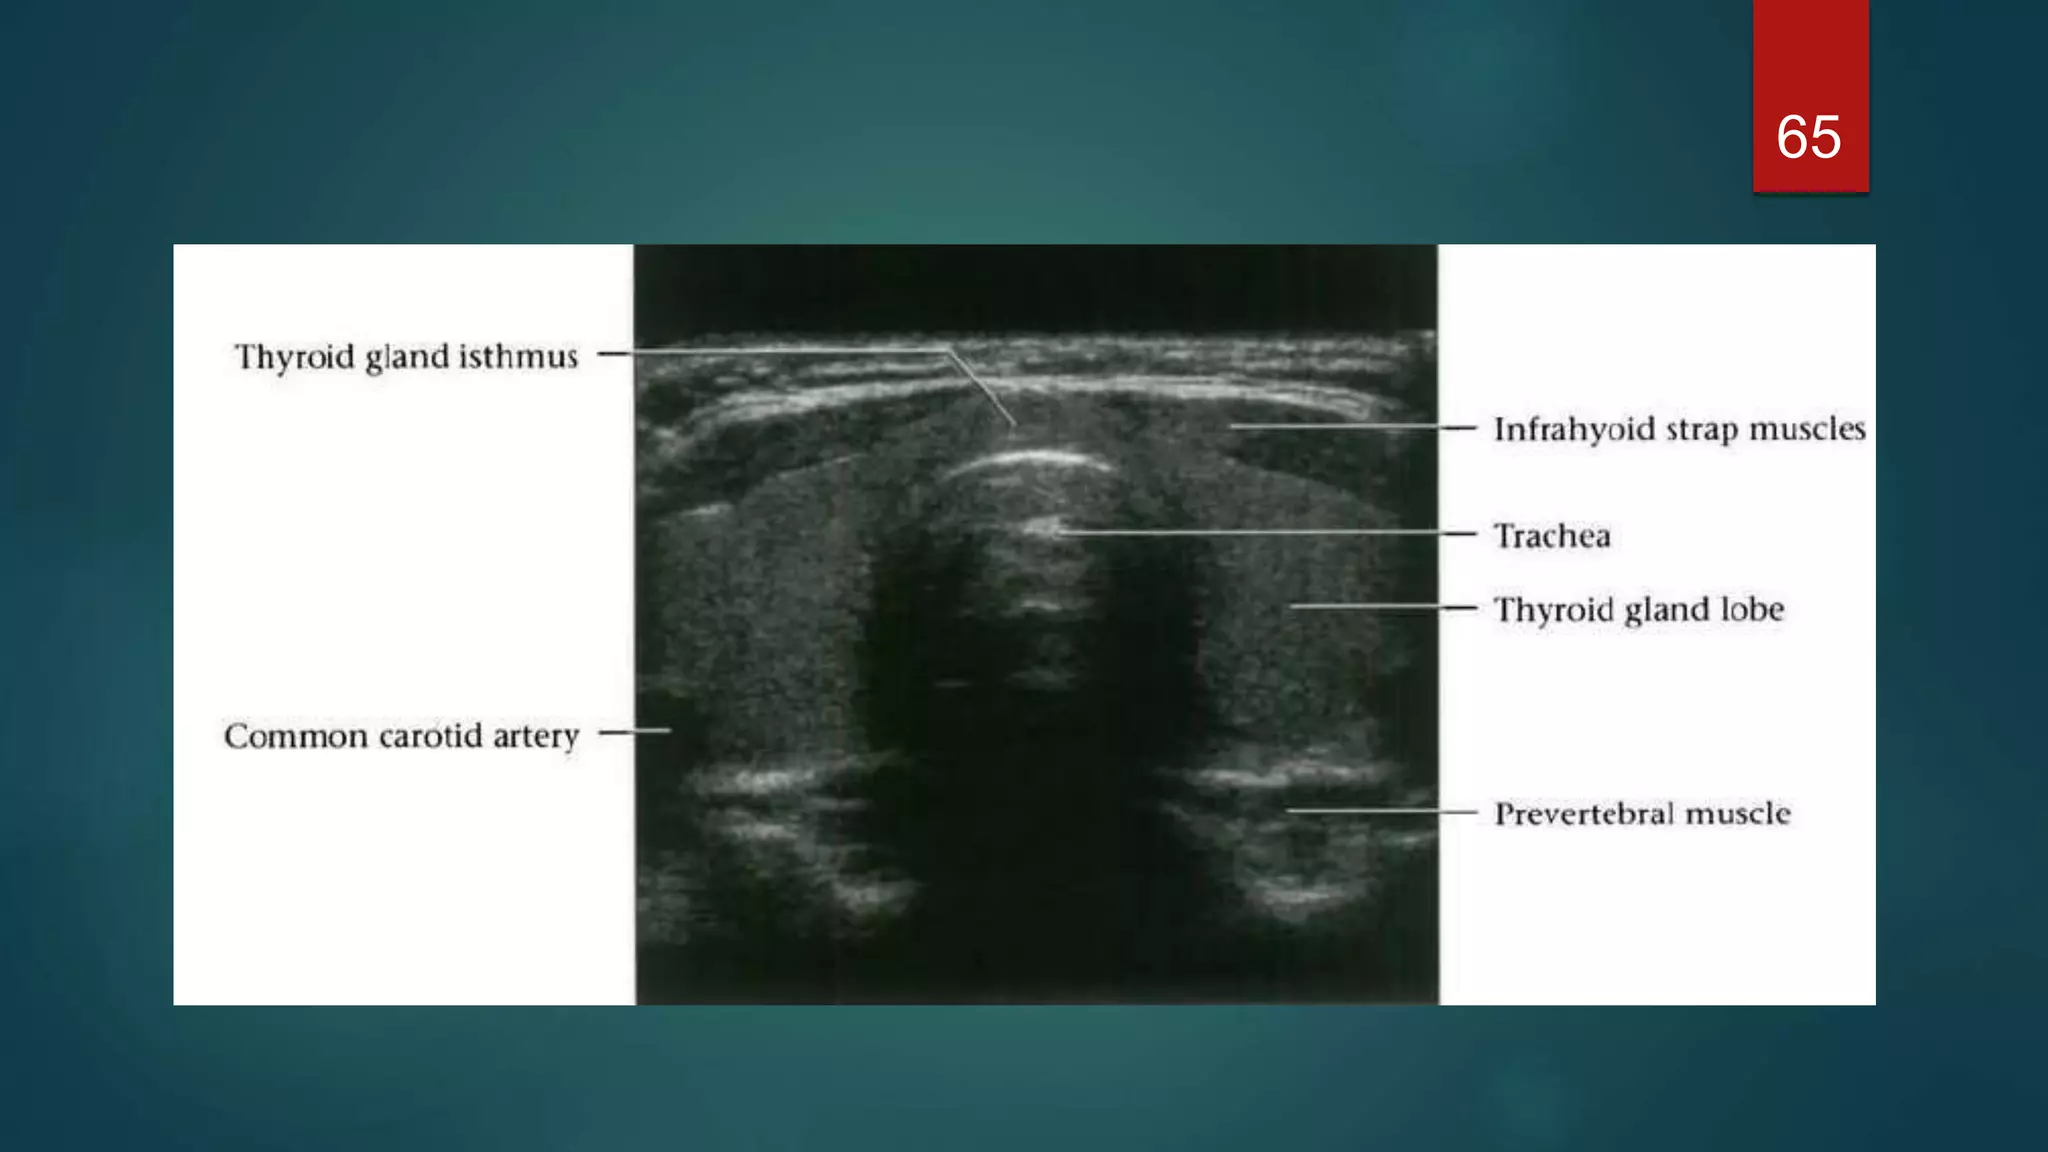

 The thyroid gland consists of two lateral lobes joined by a midline isthmus, and

lies anterior and lateral to the trachea.

 The lobes extend from the thyroid cartilage superiorly to the sixth tracheal ring

inferiorly

 Posterolaterally are the neck vessels, Behind these, on either side, are the

prevertebral muscles

 Anterior to the gland are the strap muscles of the neck and the sternomastoid

muscles

65